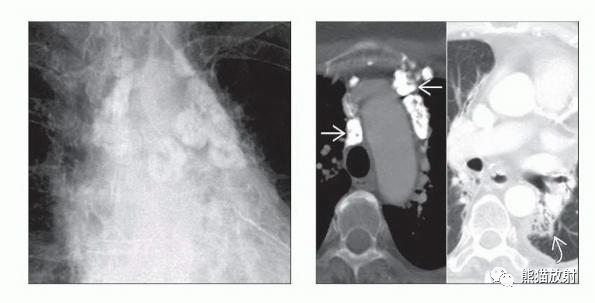

(左) 原发性纵隔大B细胞NHL和上腔静脉综合征(SVC综合征),PA胸片显示纵隔弥漫性两侧增大伴边缘分叶。

(右) 同一患者,CECT显示前纵隔巨大肿块(>10cm),密度均匀,占位效应明显,上腔静脉呈裂隙样,肿瘤累及腔内(直箭),产生SVC综合征。尽管诊断时肿瘤体积较大,但这些肿瘤往往为早期疾病。

(左) PA胸片显示原发性纵隔大B细胞NHL表现为前纵隔较大肿块,边缘有分叶。

(右) 同一患者,PET/CT显示前纵隔肿块FDG显著摄取,可见中央坏死区,双侧锁骨上区淋巴结肿大。当邻近淋巴结受累时,远处淋巴结受累则提示纵隔大B细胞NHL是弥漫性而不是原发性。